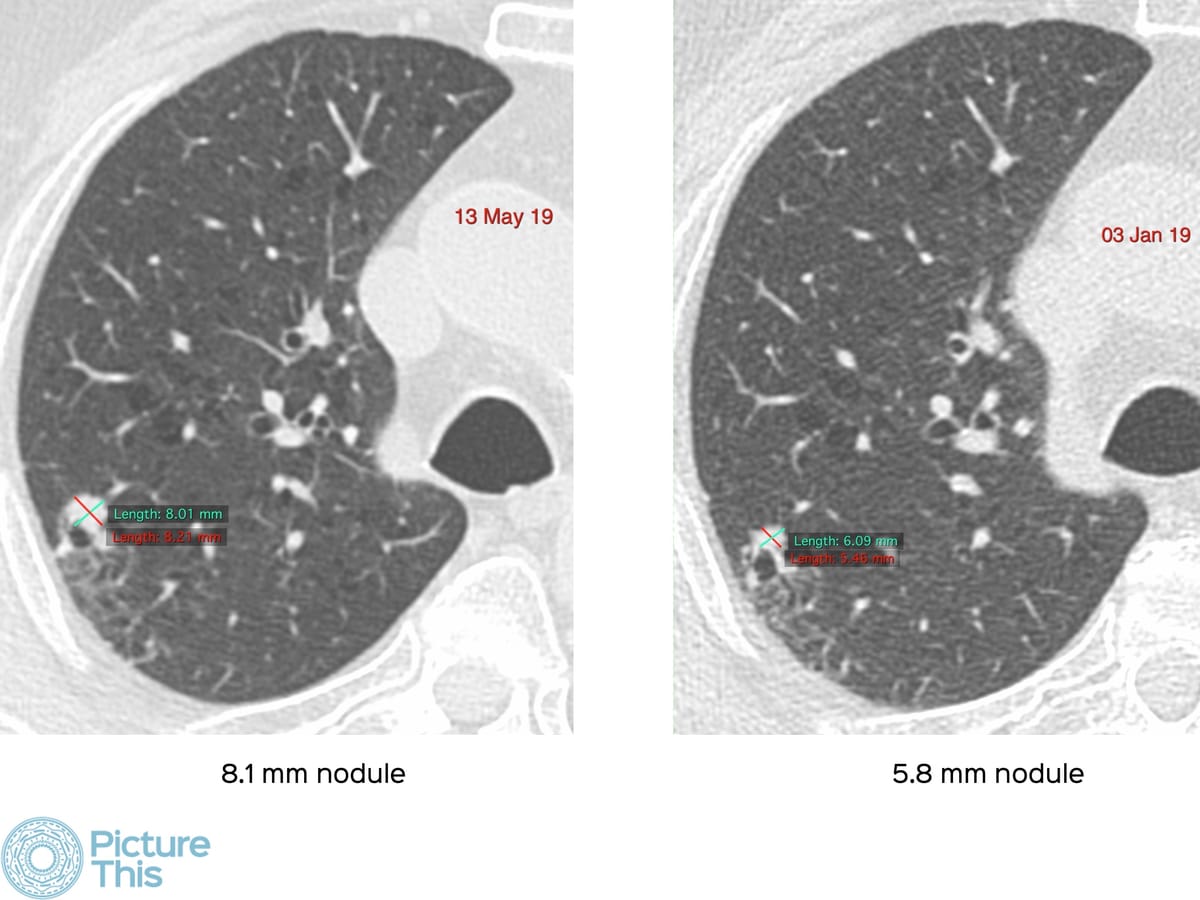

The main focus of the lecture is the pickup of active latent, asymptomatic lesions in smokers that turn out to be TB lesions that need treatment - are these false positives or are these part of the process of picking up nodules that need treatment, whether cancer or TB?